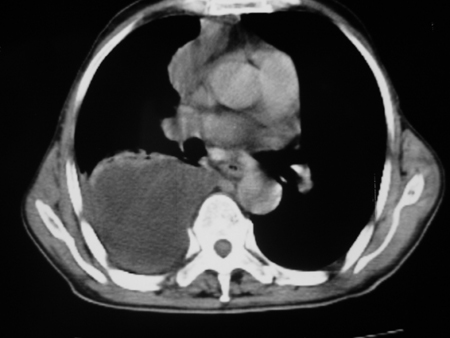

男77岁,胸痛就诊

右侧胸腔积液,部分包裹,右下肺膨胀不全,右下肺感染。

考虑右肺门占位并下叶不张 右胸包裹积液

右肺中叶及下叶炎症并胸腔积液(部分包裹),建议抽液后复查ct除外占位。

右侧胸腔积液,部分包裹,右下肺膨胀不全,右下肺感染